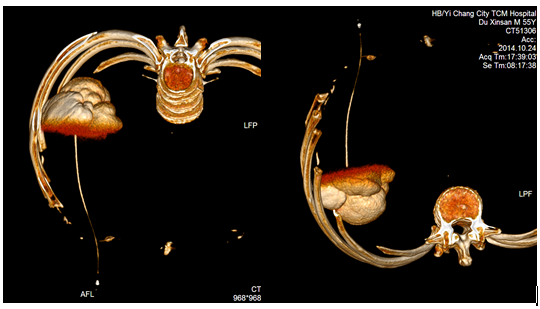

肝、肾囊肿是常见疾病,药物治疗基本无效,外科手术创伤大,费用高,并发症高,在影像学引导下穿刺引流及硬化治疗现在已为首选治疗。

典型病例、患者、男、55岁,因发现巨大肝囊肿,在我院介入科行CT引导下穿刺引流+硬化治疗术后恢复良好。